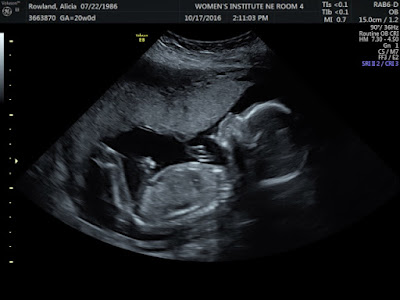

20 Weeks - It's a BOY!

It's a BOY!

We found out about a week and a half ago we were having a boy this time, and boy were we shocked! Obviously you know there's a 50% chance either way and neither of us really felt 100% this baby was a girl but.. we both always deep down saw ourselves as a family of girls.  We were both speechless when it popped up, and I definitely saw it was a boy right away! I think the biggest shock was because all of my pregnancy symptoms were IDENTICAL.  So basically my body hates pregnancy no matter what the gender! lol  I know Lance is excited to have a boy to do "guy stuff" with, but he was even like, "wait what? I thought I would be Lance and his 2 girls!" haha  Surprise!!!

Best moment of this month: Seeing our baby and learning it's a sweet little BOY!